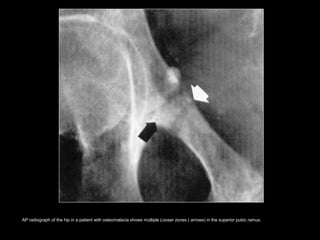

OsteomalaciaOsteomalacia

Looser's zone.Looser's zone.

• Linear areas of undermineralized

osteoid that occur in a bilateral and

symmetric distribution.

• Characteristic sites; inner margins of

femoral neck, proximal ulna, axillary

margin of the scapula, pubic rami, and

ribs.

• DDx; Paget's disease or fibrous

dysplasia.

AP radiograph of the hip in a 50-year-old man with osteomalacia shows coarsened trabecular pattern with indistinct trabeculae.

AP radiograph of the hip in a patient with osteomalacia shows multiple Looser zones ( arrows) in the superior pubic ramus.